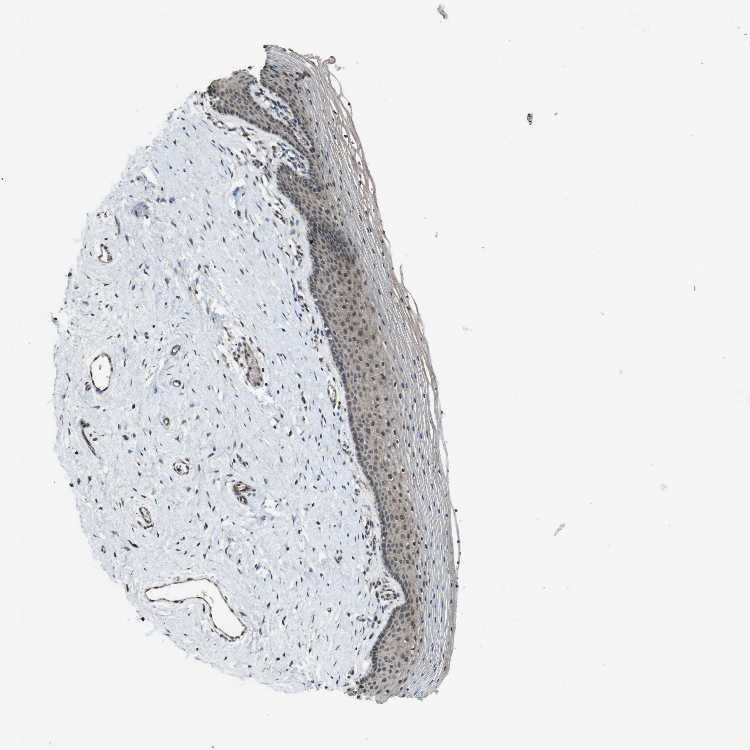

VAGINA - Antibody stainingi

Antibody staining in the annotated cell types in the current human tissue is reported as not detected, low, medium, or high, based on conventional immunohistochemistry profiling in selected tissues. This score is based on the combination of the staining intensity and fraction of stained cells.

Each image is clickable and will lead to virtual microscopy that enables deeper exploration of all samples and also displays staining intensity scores, fraction scores and subcellular localization as well as patient and tissue information for each sample.

Antibody CAB010355

Squamous epithelial cells Low